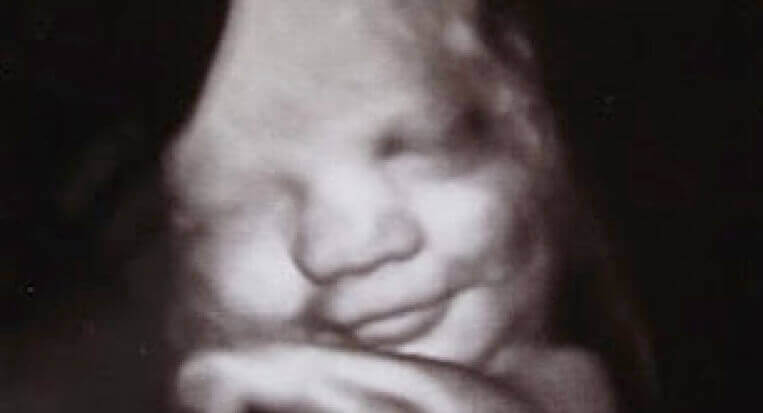

Gizemleri duygular kadar ortaya çıkan çok az şey vardır. Duygularımız ayrıca kültürümüzün, eğitimimizin, cinsiyetimizin ve ülkemizin bir parçasıdır. Bununla birlikte, genetik tabanımıza zaten entegre olmuşlardır. İngiltere’deki Durham ve Lancaster üniversiteleri bunu göstermek için çok güzel bir çalışma yürüttü. Bu çalışmada anne karnındaki fetüslerin çeşitli duyguları ifade ettikleri gözlenmiştir.

Ultrason kullanımı sayesinde, doğmamış bebeklerin gülümsediğini ve hatta ağlamayla ilgili ifadeleri gösterdiklerini keşfetmişlerdir. Bu, ana rahmi gibi sessiz ve sakin bir yerde bile, insanların çoktan “harekete geçmeye” başladığını kanıtlıyor. Hayatta kalmalarını garanti edecek bu içgüdüsel ve temel dilde eğitime başlıyorlar. Tek bir gülümseme, refahı ve memnuniyeti göstermeye yardımcı olacaktır. Ağlamak, etkin bir “alarm sistemi” olarak işlevini yerine getirecektir. Bu sayede bebek en temel ihtiyaçlarını ifade edecektir.